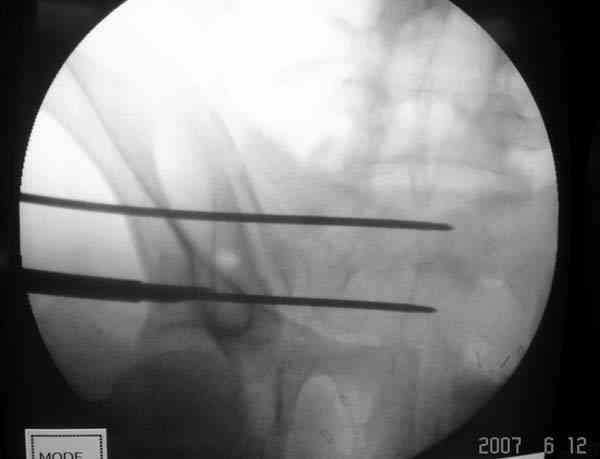

Применение длинных (7 мм каннюлированных, с резбой на всем протяжении от компании Mercury) шурупов, проведенных между двумя илиосакральными сочленениями нейтрализирует деформацию до наступления сращения.

На другом конце затягивание гайкой создает эффект болта-стяжки.

Сверло-направитель в 3.2 мм проводится вручную без применения дрели, и длина в 46 см обычно достаточна до захвата следующего илио-сактрального сочленения.

Sacroiliac screw placement

Inlet view

Проведение сверла под неврологическим мониторингом уменьшает риск повреждения нервов во время операции.